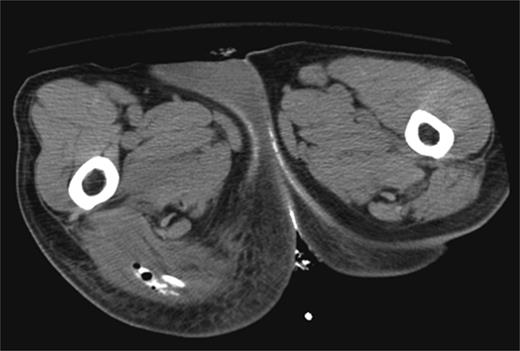

In the 6-week follow-up, repeat CT demonstrated eccentric thickening of the rectosigmoid with interval development of an adjacent complex pelvic fluid collection with supralevator extension measuring 3.5 × 2.5 cm (Fig. 2a and b). Percutaneous needle biopsy revealed pus, and a drainage catheter was left in place (Fig. 3a and b). The patient did not improve, was reimaged and was found to have collection extending into the ischiorectal fossa and supralevator space (Fig. 4). Owing to refractory pain and persistent leukocytosis, the patient was taken to the operating room for examination under anesthesia. No fistulous tract or internal drainage was noted within the rectal vault; however, consistent with the imaging, external induration was observed along the right ischiorectal fossa, where, upon incision, a large purulent cavity was evacuated. On evening rounds, the patient was noted to have a marked leukocytosis and frank stool coming from the ischial wound, and he was taken emergently to the operating room for diagnostic laparotomy where a perforated diverticulum adherent to the pelvic sidewall was identified (Fig. 5). Therefore, a Hartmann procedure, drainage of supralevator abscess, irrigation and debridement of the right ischiorectal wound, was performed.

(a) Repeat CT at 6 weeks showing supralevator abscess formation (white asterisk). The levator ani muscle is illustrated by white arrow (b) coronal image of complex supralevator collection. Arrow points to the levator ani muscle.

(a) CT-guided percutaneous drainage of perirectal abscess (b) fluoroscopic drain study showing contrast extending into the supralevator space.